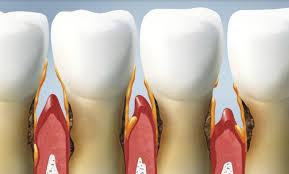

Full Analysis and Provisional Diagnosis

Based on the X-ray appearance, the most likely findings include: